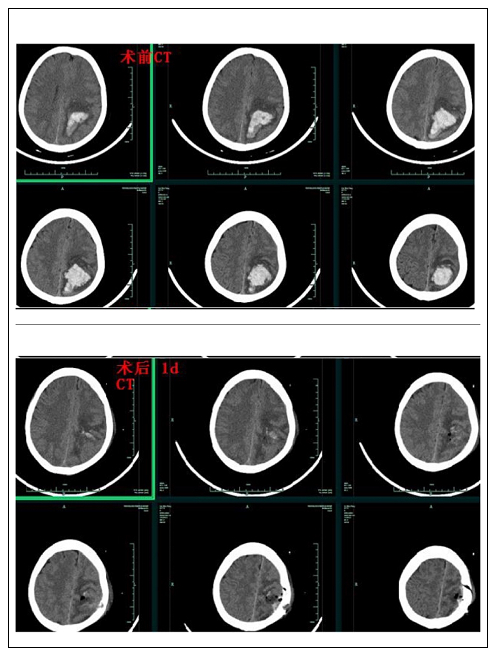

患者二:女性,57岁。脑内大量血肿量约36ml,左额顶功能区受压明显,右侧完全性偏瘫(肌力0级)。在急诊脑血管造影排除颅内血管畸形后,行神经内镜微创脑内血肿清除术,术后第10天,右下肢肌力恢复至3级,上肢恢复至1级,转康复医院继续康复治疗。